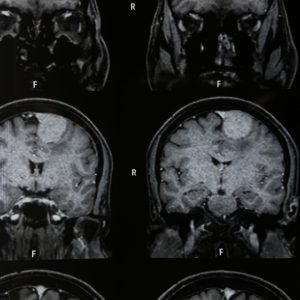

Photo Gallery